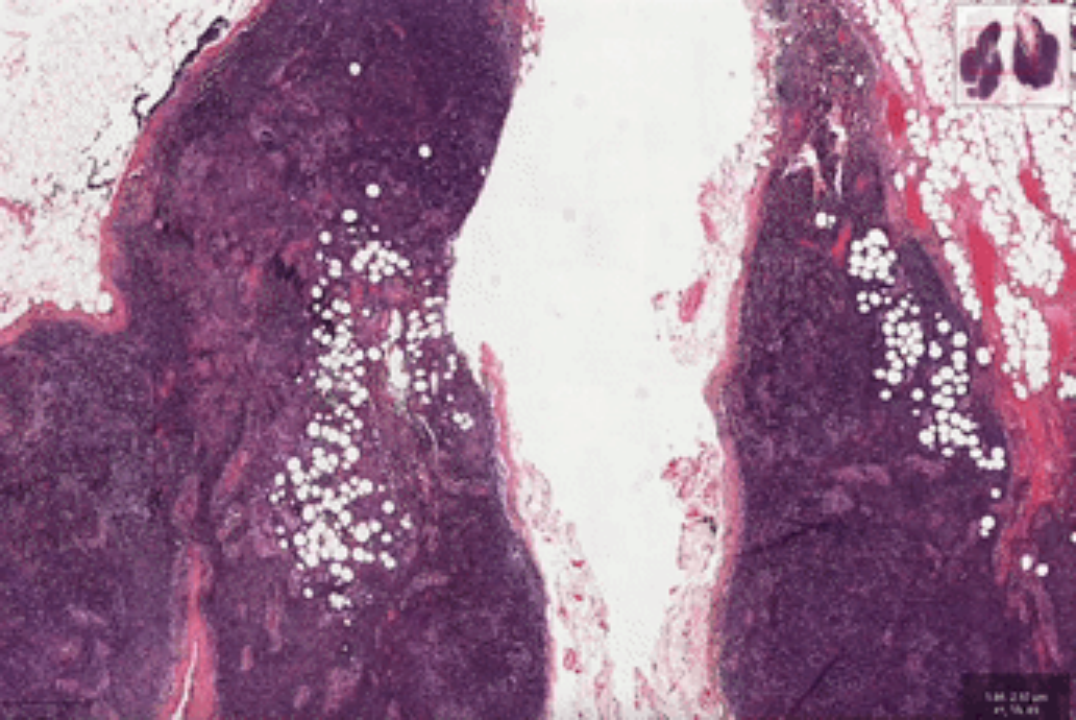

数据显示,显微扫描仪生成的高分辨率图像往往能够达到每个像素0.25微米,每张图像的尺寸经常是几万乘几万像素甚至更高,虽然这能更全面地展现切片信息,却也给医生的阅片带来了更大的压力,他们要从布满密集细胞和组织的超大尺寸图像中,肉眼找到风险的病灶位置并进行判断,“大海捞针”式的工作难度可想而知。

在高清病理图像中,病灶区域可能仅占很小的比例。

实际上,病理医生在对切片进行判读时,并不需要像这些计算机算法这样去观察高倍镜下的每一个角落。病理医生往往先利用显微镜在低倍镜下进行扫片,在高倍镜下确认相关区域,必要时可以灵活切换不同倍镜进行复核,根据经验决策最优的查看路径,以最终完成全片判读并定位到关键病灶。

受此启发,“绝悟RLogist”创新性的尝试了一种类似医生病理阅片的决策思路,采用了基于深度强化学习的,找寻最优看片路径的方法,避免了用传统的穷举方式去分析局部图像切块,而是先决策找到有观察价值的区域,并通过跨多个分辨率级别获得代表性特征,以加速完成全片判读。

实验结果表明,与典型的多实例学习算法相比,“绝悟RLogist”在观察路径显著变短情况下,能够实现接近的分类表现,决策效率提升400%。同时,该方法具有较好的可解释性。通过将RLogist的决策过程可视化,有潜力应用于教育性或者辅助性的医疗诊断场景。